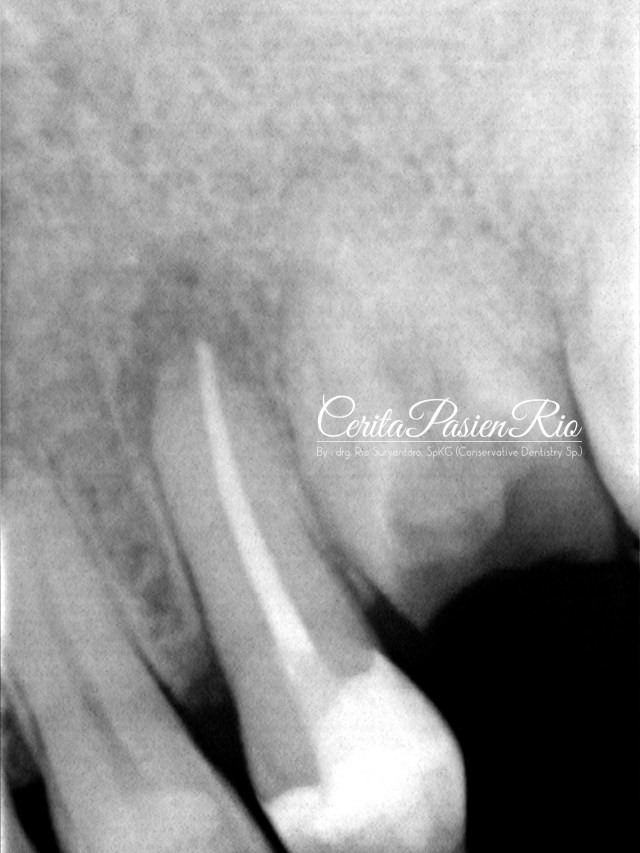

gambar 21. evaluasi radiograf pasca pengisian saluran akar. tampak integrasi tepi tambalan resin komposit kelas 2 yang baik, coronal seal yang juga beradaptasi yang baik dengan gutta percha dan gigi.